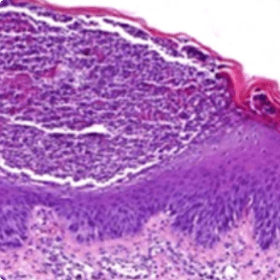

Dans les cas de psoriasis plus atypiques, une biopsie de la peau pourrait être utile10

des pustules spongiformes vasculaires.

Pustules spongiformes vasculaires